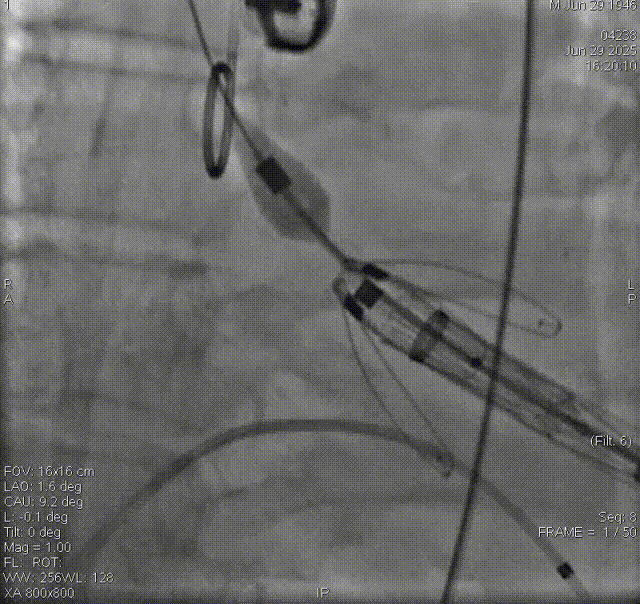

夹持件顺利入窦

瓣膜释放、解离